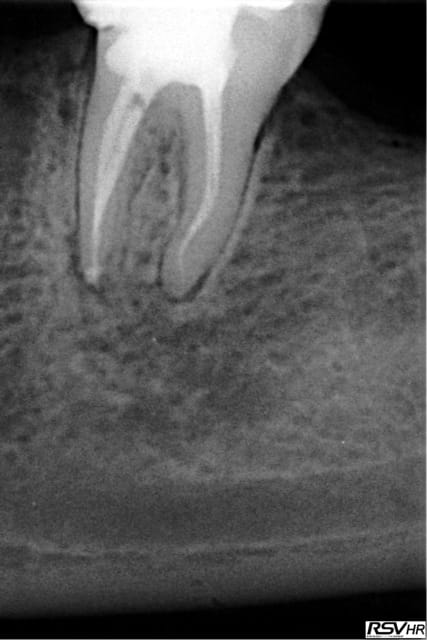

La double courbure en distal m'as donné du mal!

Pas de soucis particulier mais arthrite post op. Je crois que je vais me régler à 1 mm de l'apex radiologique désormais.